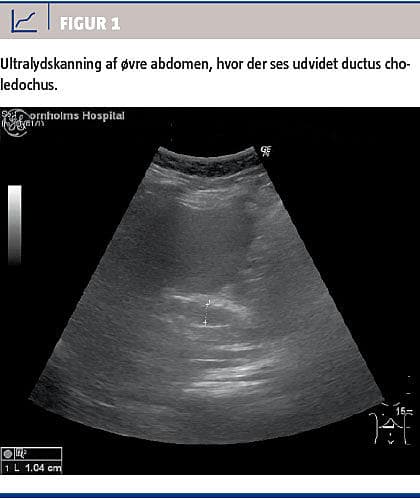

Ved en akut ultralydskanning af abdomen påviste man galdesten uden fortykkelse af galdeblærevæggen og dilateret ductus choledochus til omtrent 10 mm (Figur 1).